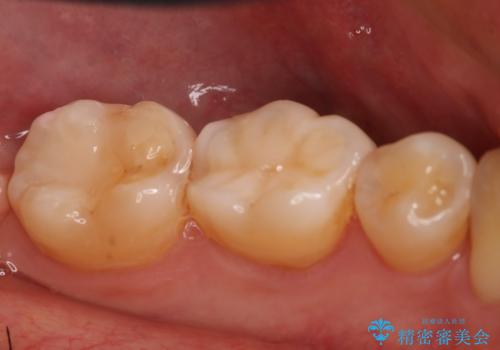

- 左下7番のCR劣化を自費治療にて希望された患者様です。

切削量を考慮してセラミックインレーでの治療を選択しました。

CR直下と隣接面にう蝕が進行していたので、除去した上で形成、印象しています。